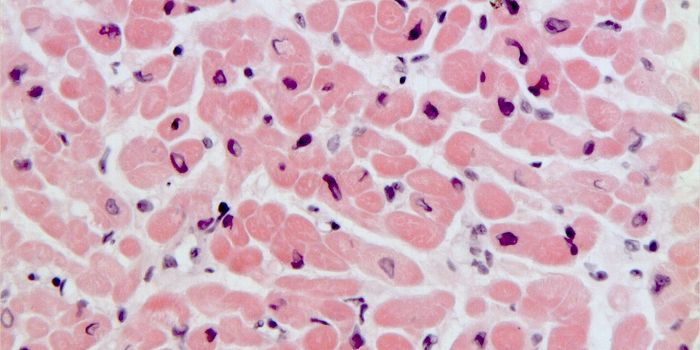

MAR 26, 2017Clinical & Molecular DXLab-grown red blood cells are not a new concept. But culturing enough of these cells in mass quantities was the main cha ...